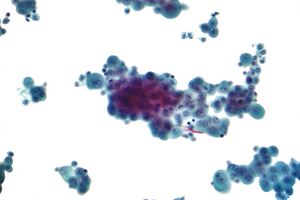

Diagnosing mesothelioma is often difficult because the symptoms are similar to those of a number of other conditions. Diagnosis begins with a review of the patient's medical history. A history of exposure to asbestos may increase clinical suspicion for mesothelioma. A physical examination is performed, followed by chest X-ray and often lung function tests. The X-ray may reveal pleural thickening commonly seen after asbestos exposure and increases suspicion of mesothelioma.[15] A CT (or CAT) scan or an MRI is usually performed. If a large amount of fluid is present, abnormal cells may be detected by cytopathology if this fluid is aspirated with a syringe.[11] For pleural fluid, this is done by thoracentesis or tube thoracostomy (chest tube); for ascites, with paracentesis or ascitic drain; and for pericardial effusion with pericardiocentesis. While absence of malignant cells on cytology does not completely exclude mesothelioma, it makes it much more unlikely, especially if an alternative diagnosis can be made (e.g., tuberculosis, heart failure).[بحاجة لمصدر] However, with primary pericardial mesothelioma, pericardial fluid may not contain malignant cells and a tissue biopsy is more useful in diagnosis.[11] Using conventional cytology diagnosis of malignant mesothelioma is difficult, but immunohistochemistry has greatly enhanced the accuracy of cytology.[بحاجة لمصدر]

Immunochemistry

Immunohistochemical studies play an important role for the pathologist in differentiating malignant mesothelioma from neoplastic mimics, such as breast or lung cancer that has metastasized to the pleura. There are numerous tests and panels available, but no single test is perfect for distinguishing mesothelioma from carcinoma or even benign versus malignant. The positive markers indicate that mesothelioma is present; if other markers are positive it may indicate another type of cancer, such as breast or lung adenocarcinoma. Calretinin is a particularly important marker in distinguishing mesothelioma from metastatic breast or lung cancer.[12]